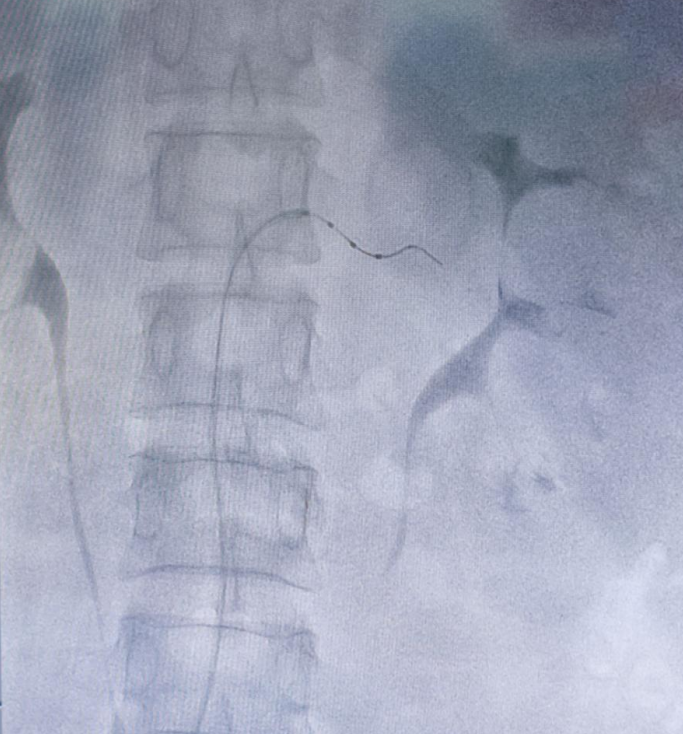

手术当天,张龙岩教授在副主任医师龚俊的配合下,麻醉后通过股动脉穿刺,沿指引导丝将消融导管分别送至双侧肾动脉以及各个分支,成功消融 12 次,30 余个靶点。消融后无肾动脉痉挛、血管夹层、迷走神经亢进等不良反应,不到一个小时手术便成功完成。术后经过一天观察,患者血压即刻下降。